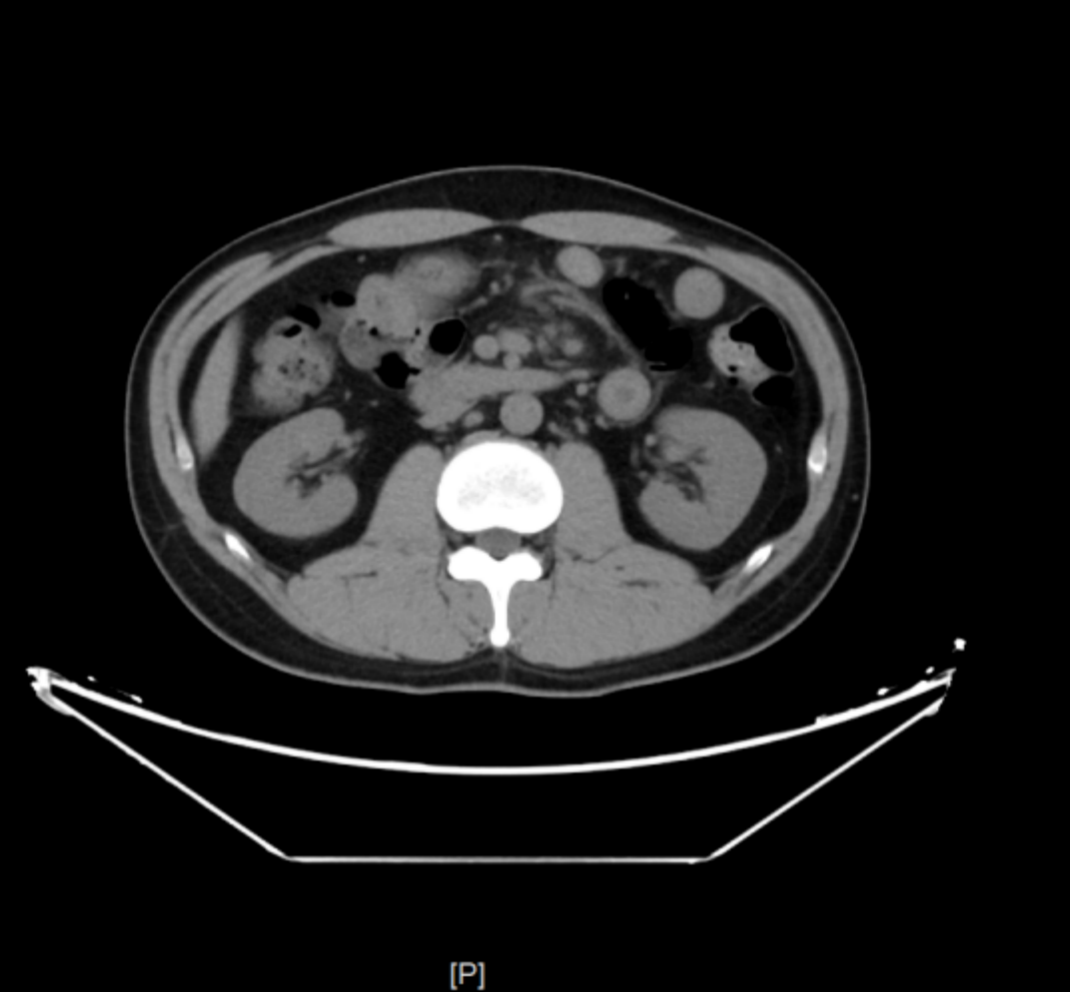

麻醉胃镜(图3

糜烂性胃炎(胃窦);胃窦溃疡A2期;十二指肠多发溃疡A2期,十二指肠黏膜发白。

图3a 胃镜示十二指肠黏膜发白

图3b 胃镜示十二指肠球部溃疡

胃镜病理

1、(胃窦黏膜活检组织)浅表黏膜慢性炎(++)伴糜烂,灶区血管壁透明变性,纤维蛋白渗出。 刚果红(-)。 2、(十二指肠水平部活检组织)小肠黏膜活动性炎伴糜烂。刚果红(-)。3、(十二指肠降部活检组织)小肠黏膜活动性炎伴糜烂,局灶脓肿形成。刚果红(-)